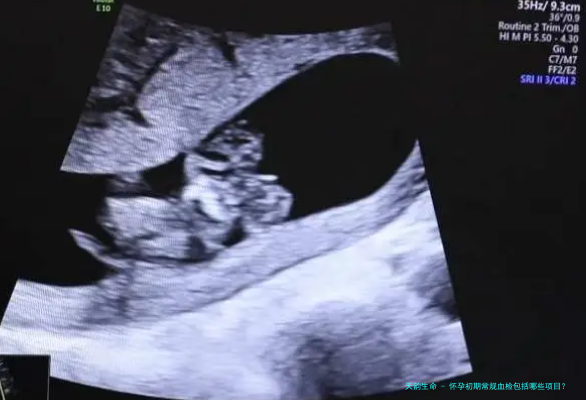

怀孕是一段特殊的时期,对于准妈妈来说,常规的血检是非常重要的,可以帮助医生了解妈妈和胎儿的健康状况。那么,在怀孕初期,常规血检需要包括哪些项目呢?